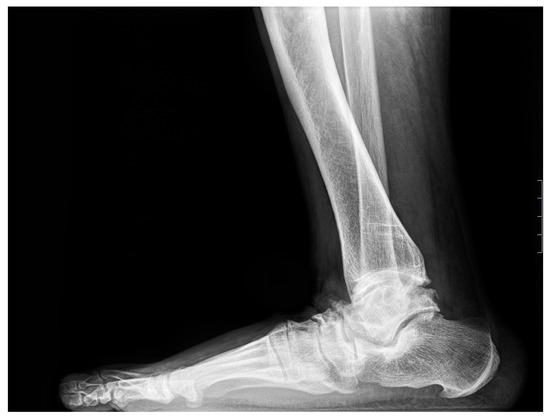

Figure 3. Lateral radiograph of the foot: 50-year-old female patient presenting with enthesopathies of the talus and navicular bones and severe JSN of the TN and NC joints.